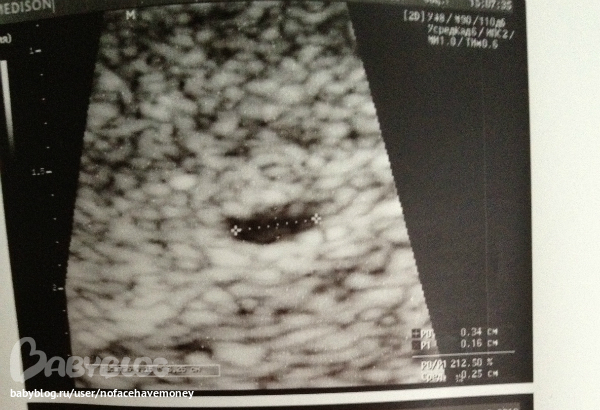

а теперь вчерашнее узи:

матка длина тела: 5,1 ( а была в прошлое узи меньше)

толщина тела 3.6 (в прошлое больше было)

эндометрий повыешнной средней, толщиной 0,8 см (8 мм) с гипоэхогенным ободком отторжения, в проекции эндометрия лоцируются анэхогенные полоста размерами до 0,3 * 0,16 см

плодное яйцо говорит толком и не выросло,ну там на буквально 1 мм, сказала что беременность вряд ли сохраниться, и еще сказала чтобы я не пила дюфастон, перестала т.е, но если это беременность то дальше будешь пить! хм.. что за издевательство над организмом ?или хрен с этим организмом ,но ведь если плодное яйцо (плод) все таки чудом выживет , а я этим временемперстану пить дюф?получается я сама же собственными руками не дам шанса своему малышу? я в замешательстве!!

вот это узи вчерашнее, плодное яйцо по ее словам толком и не выросло!

p/s сегодня только 12 дней задержки